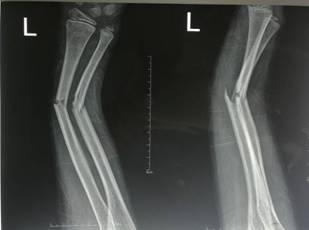

微创治疗肱骨干骨折

优点:闭合复位,不干扰骨折断端,中心固定,利于愈合。